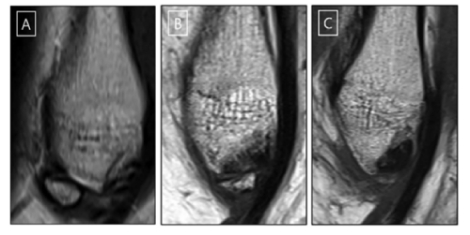

이번 연구에 참여한 만성 족관절 불안정증 환자의 타원형 뼛조각. 뼛조각이 있으면 만성 족관절 불안정증으로 이어질 가능성이 높으며, 특히 타원형인 경우 위험이 더 높은 것으로 나타났다. 사진=서울대병원

이미지 확대보기이 교수는 “이번 연구는 발목 불안정증을 호소하는 환자의 상당수에서 뼛조각이 발견됐고, 형태에 따라 보존적 치료보다 적극적 치료가 효과적일 수 있다는 사실을 밝혔다” 며 “특히 소아청소년기에 발목 외상이 생기면 뼛조각이 발생할 가능성이 높아지는 만큼, 석고 고정 등 적극적 치료가 권장 된다”고 밝혔다.